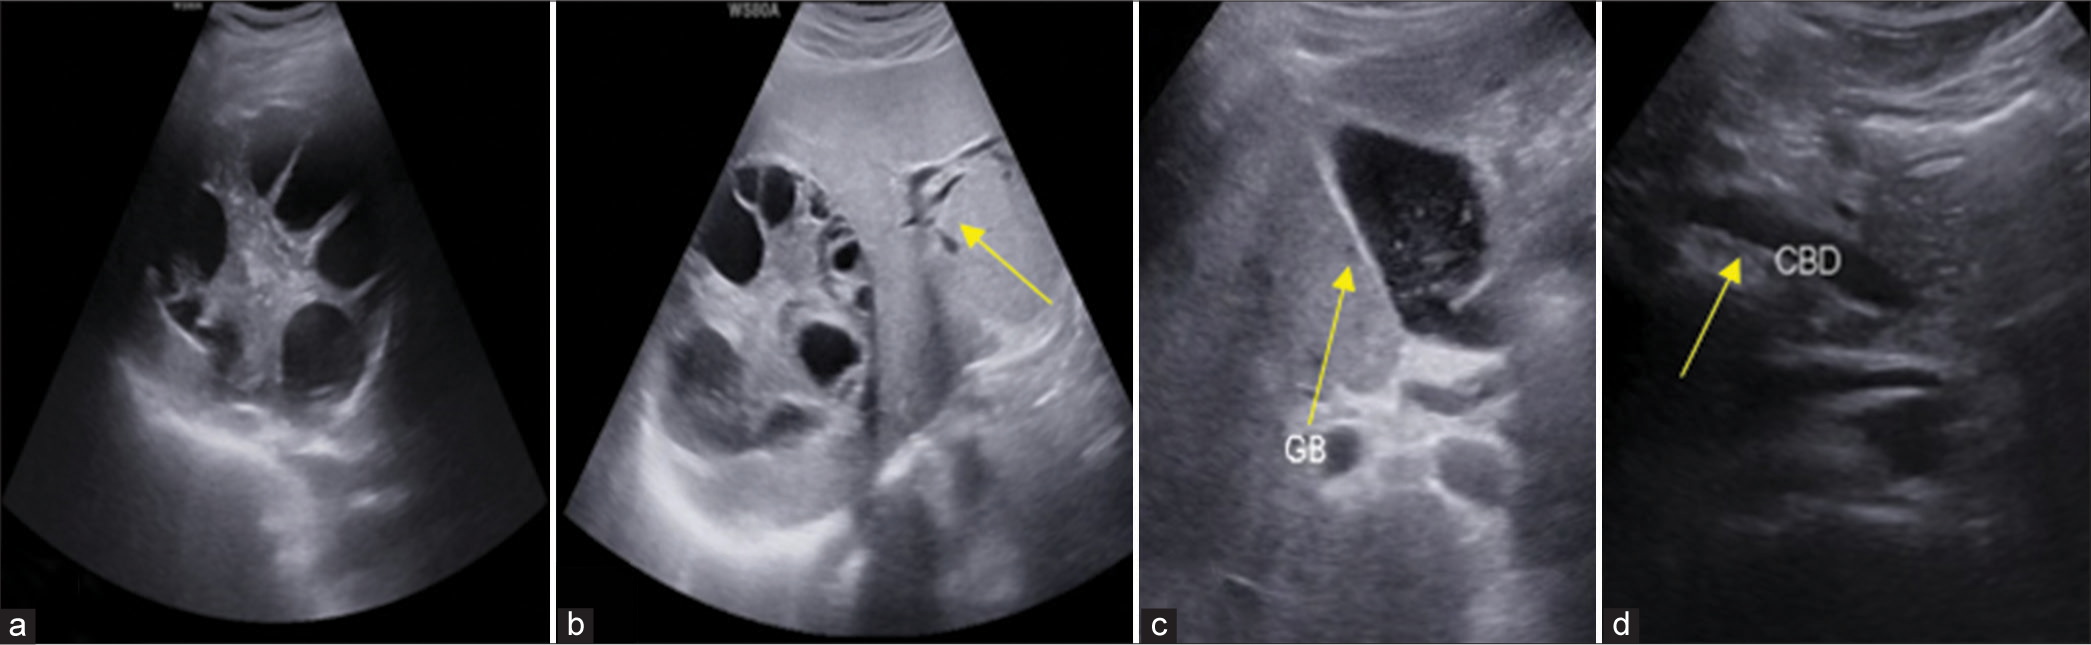

Mithun Natarajan, Seetharaman Cannane, Lokesh Vasu